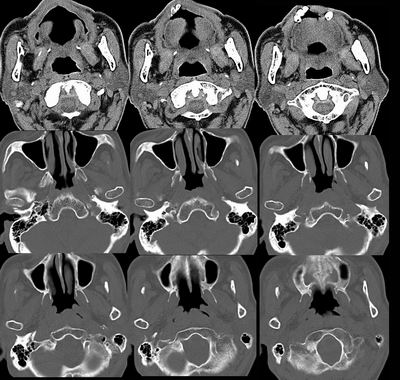

左侧头长肌增厚,突去鼻烟腔内,考虑:鼻烟ca?转移瘤?

右侧咽隐窝变浅,扫描体位不对称?还是病变?呵呵,高手何在?

右侧咽隐窝变浅,相应软组织增厚。考虑:鼻咽癌复发。

从影像学角度考虑,虽然两侧扫描时不对称,但是右侧还是存在病变,应该考虑鼻咽癌改变,与炎症鉴别----mr

右侧咽隐窝变浅,沿旁间隙存在,结合病史考虑鼻咽癌复发。

右侧咽隐窝变浅,相应软组织增厚。考虑:鼻咽癌可能。建议活检